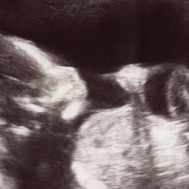

As the brain and nerve endings continue to develop, you may experiment with your sense of touch.[2] In this photo the baby is touching her ear.